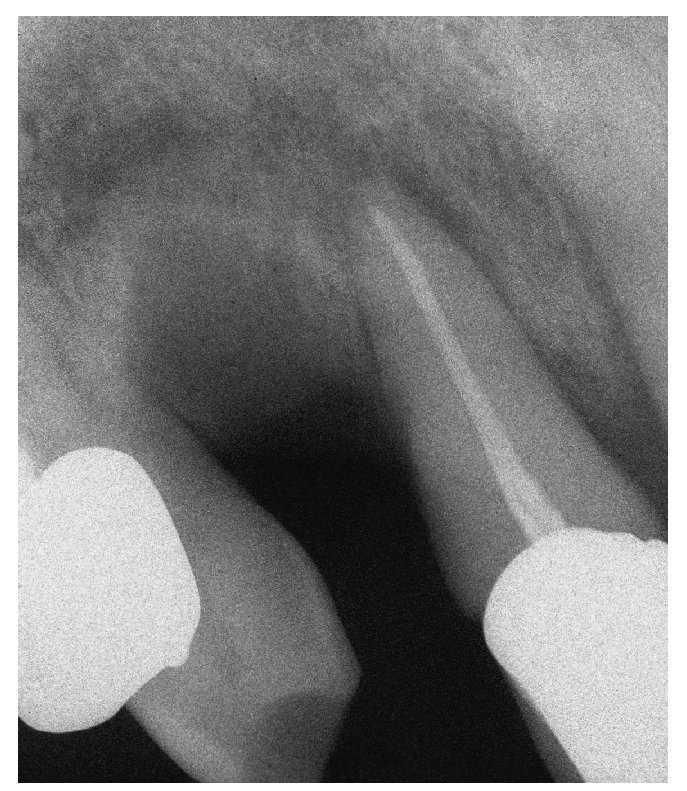

Figura 1b. En la radiografía intraoral de la región 11 a 13 se observa una región alveolar 12 no reosificada y una zona osteolítica en banda que se extiende desde el diente 11 en apical hasta el diente 13.